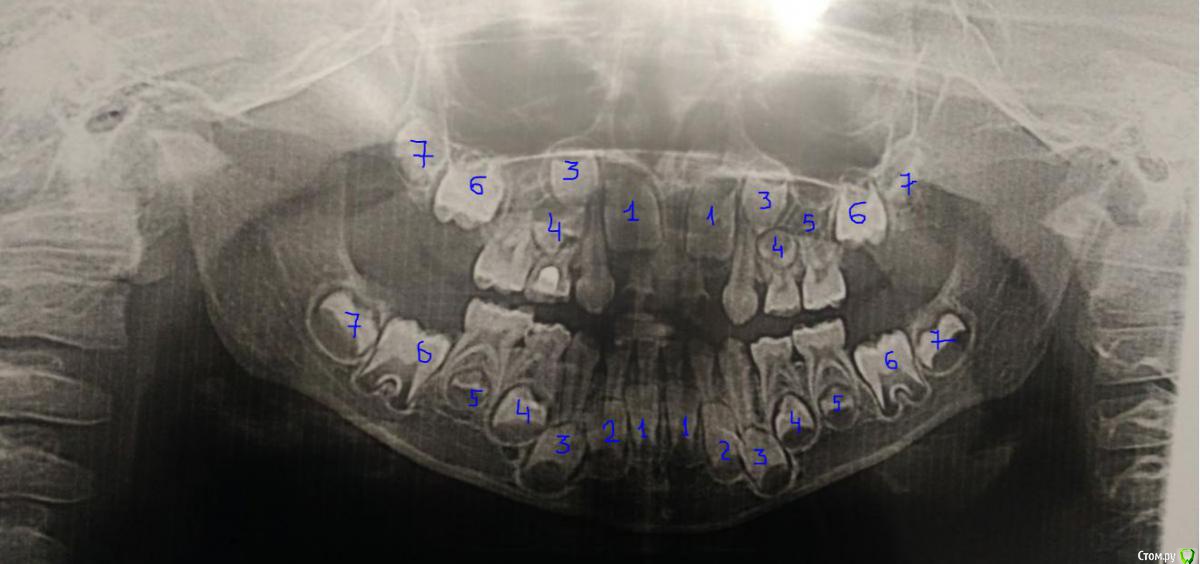

ИринаДементьева Опубликовано 11 сентября, 2018 Поделиться Опубликовано 11 сентября, 2018 Уважаемые доктора, посмотрите какие зубы постоянные отсутствуют в зачатках? Ссылка на комментарий

St. Опубликовано 11 сентября, 2018 Поделиться Опубликовано 11 сентября, 2018 Добрый день. Отсутствуют зачатки обоих верхних 2, возможно еще правой 5 ( но там пока не совсем хорошо видно на данном этапе формирования) Ссылка на комментарий

ИринаДементьева Опубликовано 13 сентября, 2018 Автор Поделиться Опубликовано 13 сентября, 2018 Добрый день. Отсутствуют зачатки обоих верхних 2, возможно еще правой 5 ( но там пока не совсем хорошо видно на данном этапе формирования)Сыну сейчас 5,10, через какое время снова лучше сделать? Ссылка на комментарий

St. Опубликовано 13 сентября, 2018 Поделиться Опубликовано 13 сентября, 2018 Наблюдайтесь у детского стоматолога в плане гигиены и лечения кариеса по необходимости. Как часто бывать на осмотрах скажет ваш доктор, стандартный промежуток 3-6 мес обычно.Снимок раньше чем через год смысла делать нет.В любом случае в плане отсутствующих зубов пока что ждать Ссылка на комментарий